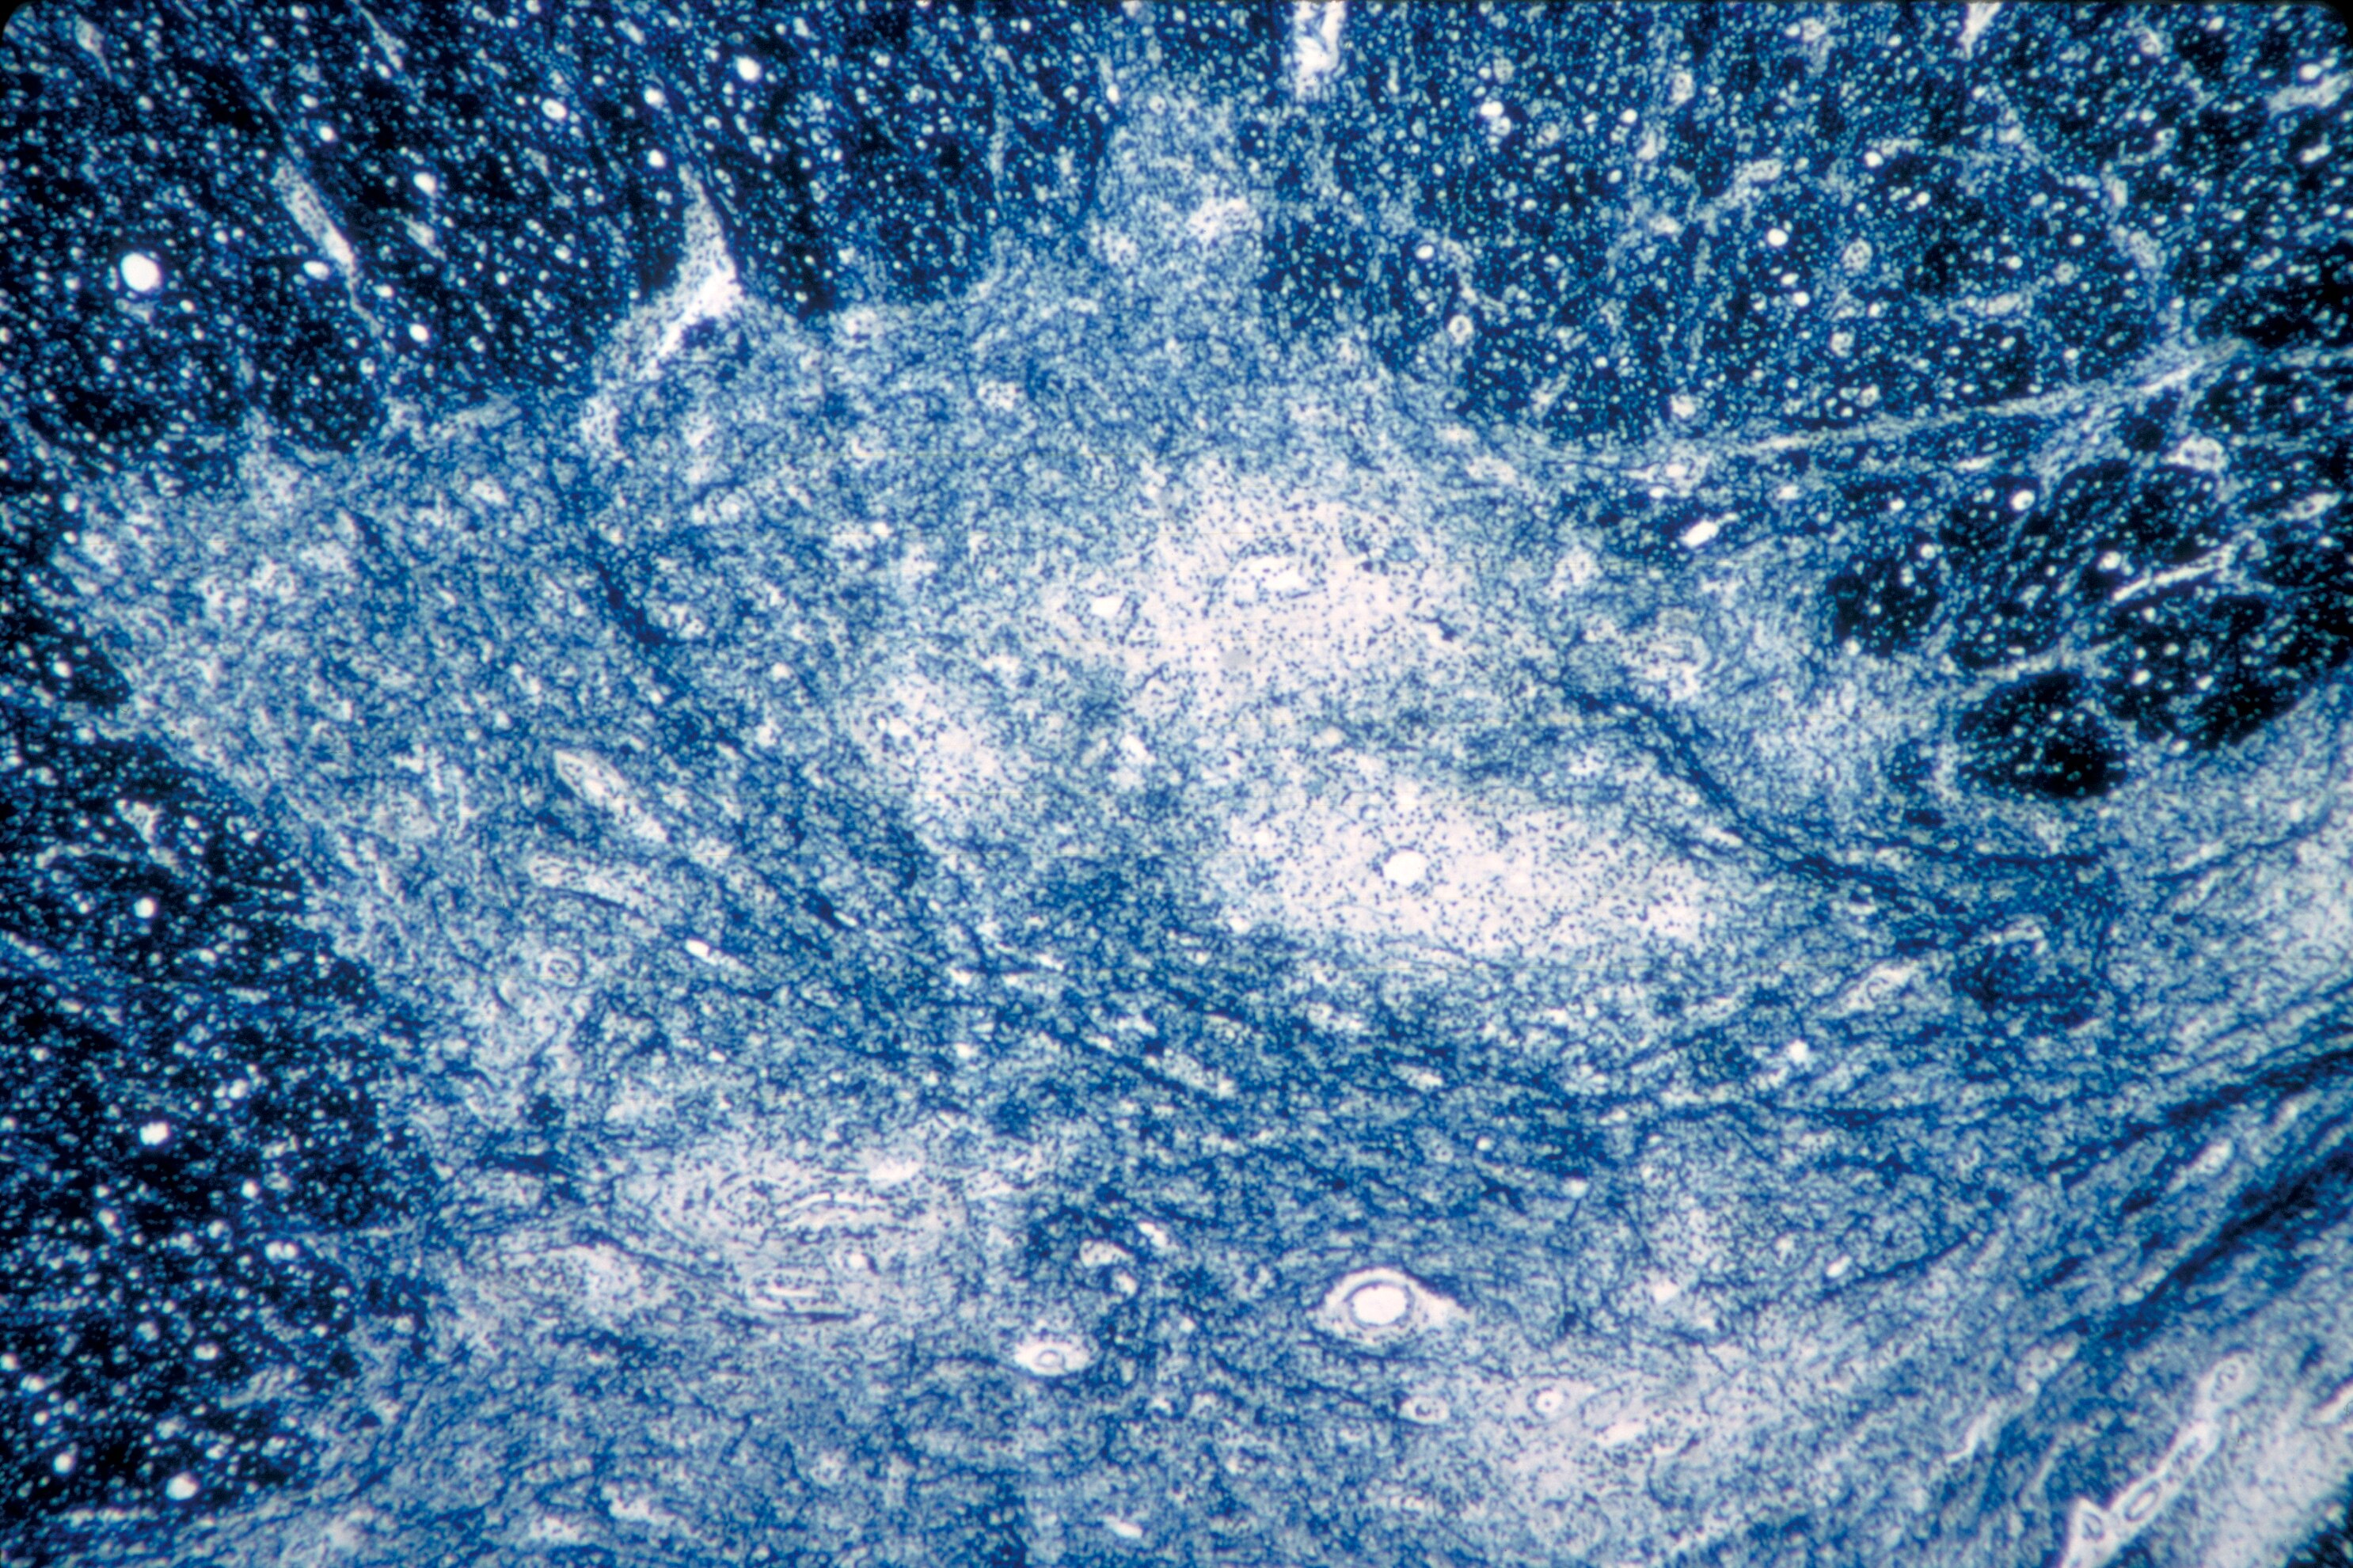

This 1964 microscope image shows damage from the polio virus to human spinal cord tissue.  (AP: CDC/Emory University/Dr Karp)

It can infect a person's spinal cord, causing paralysis and possibly permanent disability and death.